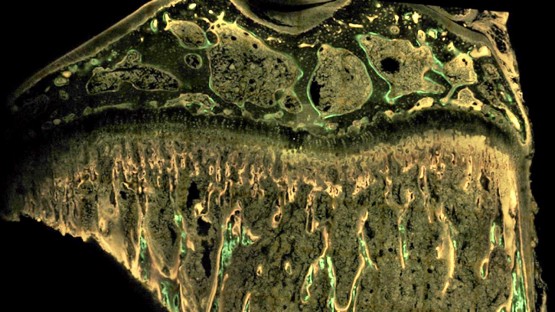

A bone cross-section is labeled with fluorescent dyes to measure the dynamics of bone formation.

They used micro-computed tomography to study the bone architecture; Raman imaging to scan the bone’s chemical spectra; and small-angle X-ray scattering (SAXS) to reveal mineral properties. Most crucially, they employed a technique called dynamic histomorphometry, in which fluorescent dyes are integrated into the bone at different intervals and essentially create time stamps that show the rate of bone formation.